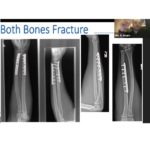

Fractures of the Forearm